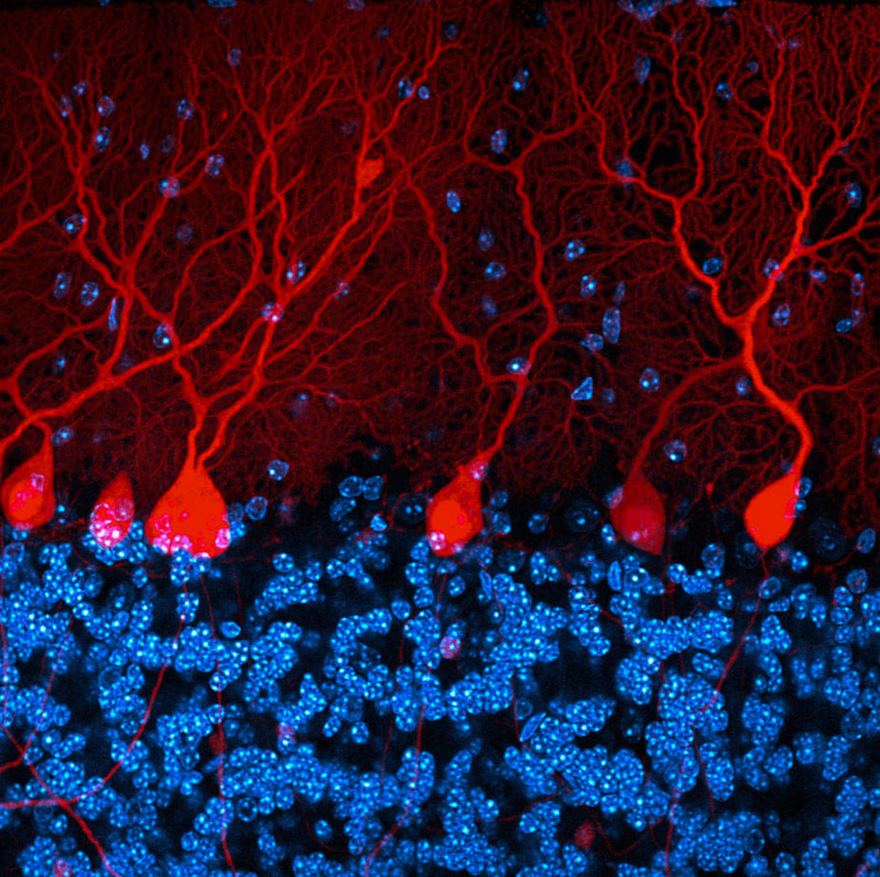

Cerebellum Brain Section Of A Rat

Section Of The Cerebellum